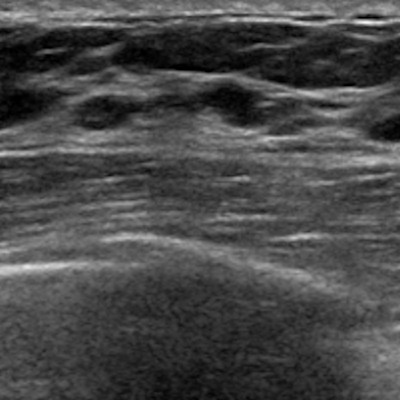

Sample images show cancer detection at supplemental ultrasound screening after screening mammography with a negative result. (A) Craniocaudal right breast screening mammography shows negative findings in a 54-year-old female patient with extremely dense breast tissue. (B) Coronal view from supplemental screening with automated whole-breast ultrasound image in the same patient four months later shows an irregular hypoechoic mass (dashed yellow circle) in the right breast, diagnosed as invasive ductal carcinoma. (C) Craniocaudal screening right breast mammography shows negative findings in a 74-year-old patient with heterogeneously dense breast tissue. (D) Antiradial gray-scale image in the right breast from supplemental handheld screening ultrasound in the same 74-year-old patient 7 months later demonstrates an irregular hypoechoic mass in the right breast (yellow outline), which yielded a diagnosis of invasive ductal carcinoma. Image courtesy of the RSNA.